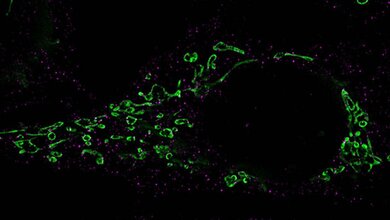

Forschende des Leibniz-Instituts für Virologie (LIV), der Universität Hamburg (UHH), und des Universitätsklinikums Hamburg-Eppendorf (UKE) am Centre for Structural Systems Biology (CSSB) in Hamburg sowie des Göttinger Max-Planck-Instituts (MPI) für Multidisziplinäre Naturwissenschaften ist es jedoch gelungen, den gB-Komplex in seiner bisher nicht zugänglichen fusionsbereiten Form zu stabilisieren. Sie konnten dessen hochaufgelöste Struktur mittels Kryo-Elektronenmikroskopie, Bildanalyse und Struktur-Modellierung bestimmen. Dabei haben die Technologieplattformen für ausgebaute Lichtmikroskopie und Kryo-Elektronenmikroskopie (Kryo-EM) am CSSB geholfen.

Das Göttinger Team isolierte aus geimpften Alpakas einen Mini-Antikörper, einen sogenannten Nanobody, der gB in bereits sehr geringen Konzentrationen neutralisieren kann. Der Nanobody bindet die fusionsbereite Form von gB und verhindert, dass es die Bewegungen ausführen und die Energie freisetzen kann, die für die Fusion erforderlich ist. Alpakas, Lamas oder anderen Kamele besitzen Antikörper, die einfacher aufgebaut sind als normale Säugetier-Antikörper. Diese lassen sich im Labor zu sogenannten Nanobodies noch weiter verkleinern. Forschende in der Gruppe von Kay Grünewald, Leiter der Abteilung Strukturelle Zellbiologie der Viren am LIV, UHH und CSSB in Hamburg produzierten eine gB-Zubereitung, mit dem das Team in Göttingen ein Alpaka immunisierte, und die Produktion von Antikörpern auslöste. „Dabei war die Belastung für unser Alpaka Max sehr gering, vergleichbar mit einer Impfung und Blutuntersuchung beim Menschen“, erklärt Dirk Görlich, Direktor am MPI und Leiter der Abteilung Zelluläre Logistik. Nach einer Blutspende war Max‘ Einsatz beendet. Die weitere Arbeit erfolgte im Labor mithilfe von Hightech-Geräten, Enzymen, Bakterien, Bakteriophagen und Computern. Schlussendlich werden Nanobodies mikrobiologisch produziert.